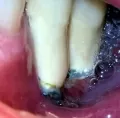

Подскажите, пожалуйста, можно ли по панорамному снимку определить правильность установки импланта? Имплант устанавливался на место шестерки, верхней челюсти, закрытый синус-лифтинг, с 1 гр. кости. Сколько по норме миллиметров должно быть между корнем зуба и имплантом? Является ли нормой, что после снятия швов, языком нащупывалась точка импланта, а вскрытие было бескровное?

В вашем случае поврежден корень зуба и необходимо срочно извлечь имплантат. Ответы на другие вопросы не актуальны. Это, что касается нижнего имплантата. На верхней челюсти я не вижу качественной операции, закрытый синус, так как имеется перфорация на 2 мм. пазухи. Рекомендую обратиться к хирургу.